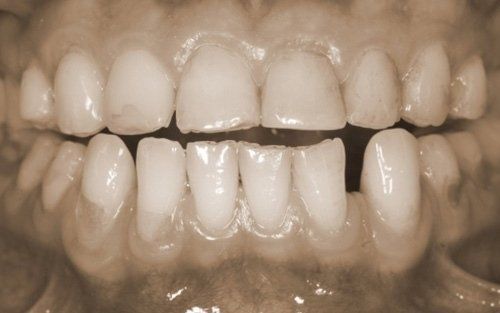

The constant presence of acidic substances causes the gradual loss of the hard tissues of the tooth

and the consequent modification of both the aesthetics of the tooth and its dimensions. The patient often begins to stop smiling, ashamed of the appearance their teeth have taken, in addition to frequently experiencing dental sensitivity that develops proportionally to the progression of the process. Sometimes this phenomenon is associated with

dental abrasion (abfraction), or abrasion may occur as a separate phenomenon. In the latter case, it is due to

mechanical forces applied to the teeth with incorrect movements and intensity. Generally, excessive horizontal tooth brushing movements and/or toothbrush bristles that are too rigid are responsible for this.